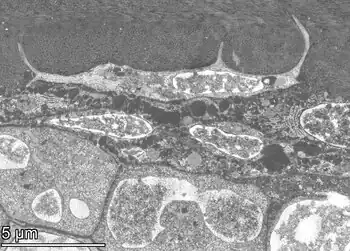

An osteocyte, an oblate-shaped type of bone cell with dendritic processes, is the most commonly found cell in mature bone. It can live as long as the organism itself.[1] The adult human body has about 42 billion of them.[2] Osteocytes do not divide and have an average half life of 25 years. They are derived from osteoprogenitor cells, some of which differentiate into active osteoblasts (which may further differentiate to osteocytes).[1] Osteoblasts/osteocytes develop in mesenchyme.

In mature bones, osteocytes and their processes reside inside spaces called lacunae (Latin for a pit) and canaliculi, respectively.[1] Osteocytes are simply osteoblasts trapped in the matrix that they secrete. They are networked to each other via long cytoplasmic extensions that occupy tiny canals called canaliculi, which are used for exchange of nutrients and waste through gap junctions.

Structure

Osteocytes have a stellate shape, approximately 7 micrometers deep and wide by 15 micrometers in length.[3] The cell body varies in size from 5–20 micrometers in diameter and contain 40–60 cell processes per cell,[4] with a cell to cell distance between 20–30 micrometers.[3] A mature osteocyte contains a single nucleus that is located toward the vascular side and has one or two nucleoli and a membrane.[5] The cell also exhibits a reduced size endoplasmic reticulum, Golgi apparatus and mitochondria, and cell processes that radiate largely towards the bone surfaces in circumferential lamellae, or towards a haversian canal and outer cement line typical of osteons in concentric lamellar bone.[5] Osteocytes form an extensive lacunocanalicular network within the mineralized collagen type I matrix, with cell bodies residing within lacunae, and cell/dendritic processes within channels called canaliculi.[6]